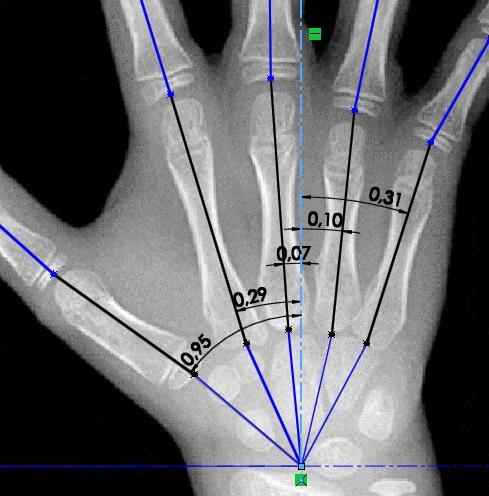

Figura 13. Carpograma de referencia con adición de líneas representando cada cadena cinemática

25

Figura 14. Toma de medidas de cada eslabón de las cadenas cinemáticas que componen la mano 26

Figura 15. Medición de ángulos entre eslabones de las cadenas cinemáticas que componen la mano

27 Tabla 4. Orientación de cada cadena cinemática sobre el carpograma de referencia

Tabla 5. Coordenadas de los vectores de orientación. 27

Posteriormente, se extienden líneas entre los puntos de análisis para cada una de las cadenas cinemáticas que componen la mano, esto con el fin de aproximar la imagen del carpograma de referencia a la representación esquemática planteada anteriormente (Figura 10), y así poder dimensionar la representación esquemática. Una vez hecho esto, se obtiene la imagen que se observa en la Figura 13.

Una vez se tiene la representación esquemática de la mano humana planteada sobre el carpograma de referencia en un software CAD, es posible realizar mediciones, las cuales permiten conocer las dimensiones en milímetros de cada uno de los eslabones de las cadenas cinemáticas (Figura 14), así como también los ángulos de orientación de cada uno de ellos (Figura 15), los cuales posteriormente se analizarán en la determinación del modelo.

Los resultados de las mediciones realizadas sobre el carpograma de referencia se presentan en las Tablas 3, 4 y 5. Se emplea para esto la nomenclatura citada en la Tabla 2.

De igual manera se mide la orientación de cada cadena cinemática respecto al eje X.

Tabla 4. Orientación de cada cadena cinemática sobre el carpograma de referencia

Ángulo [rad]

Pulgar -0,95

Indice -0,29

Medio -0,07

Anular 0,1 Meñique 0,31